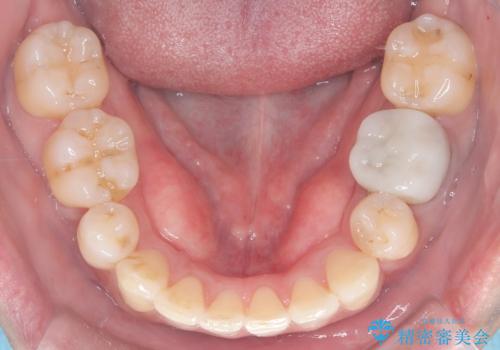

- 治療計画

重度の叢生により、抜歯を伴う矯正が必要と判断しました。目立ちにくい透明な審美ブラケットを用いたワイヤー矯正を実施しましたが、治療途中での海外出張が決定したため、一度矯正装置を取り外し、保定装置で現状維持を行いました。帰国後に改めて装置を装着し矯正を再開。患者様のライフスタイルに柔軟に対応しながら、最終的には理想的な歯並びと美しい口元を実現しました。